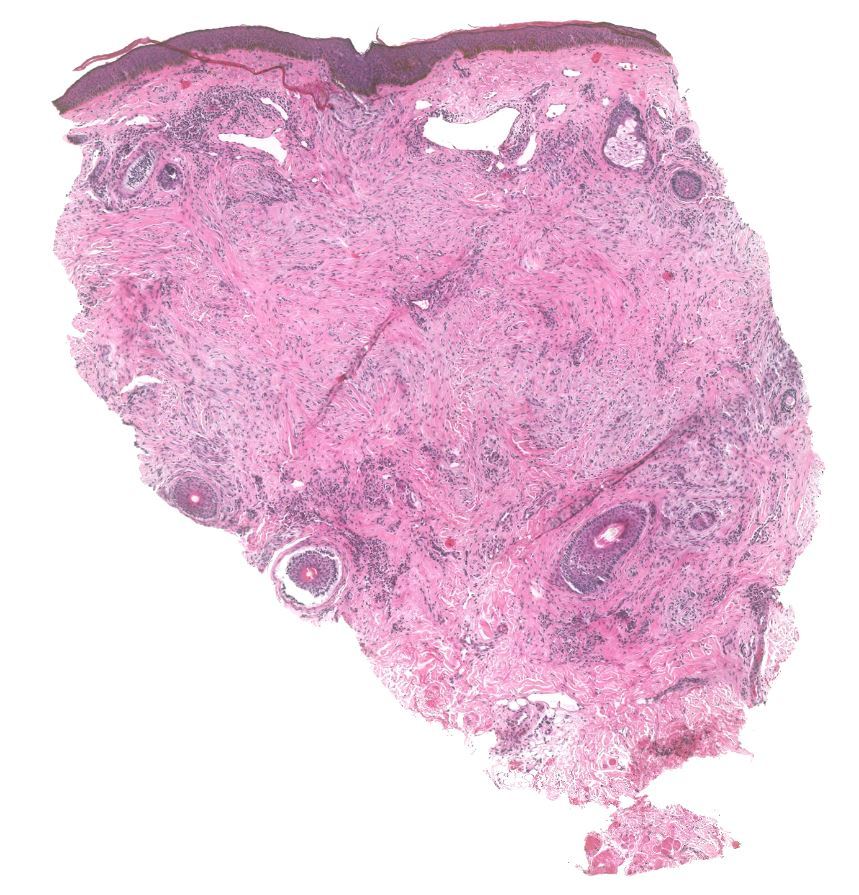

Dermatofibroma